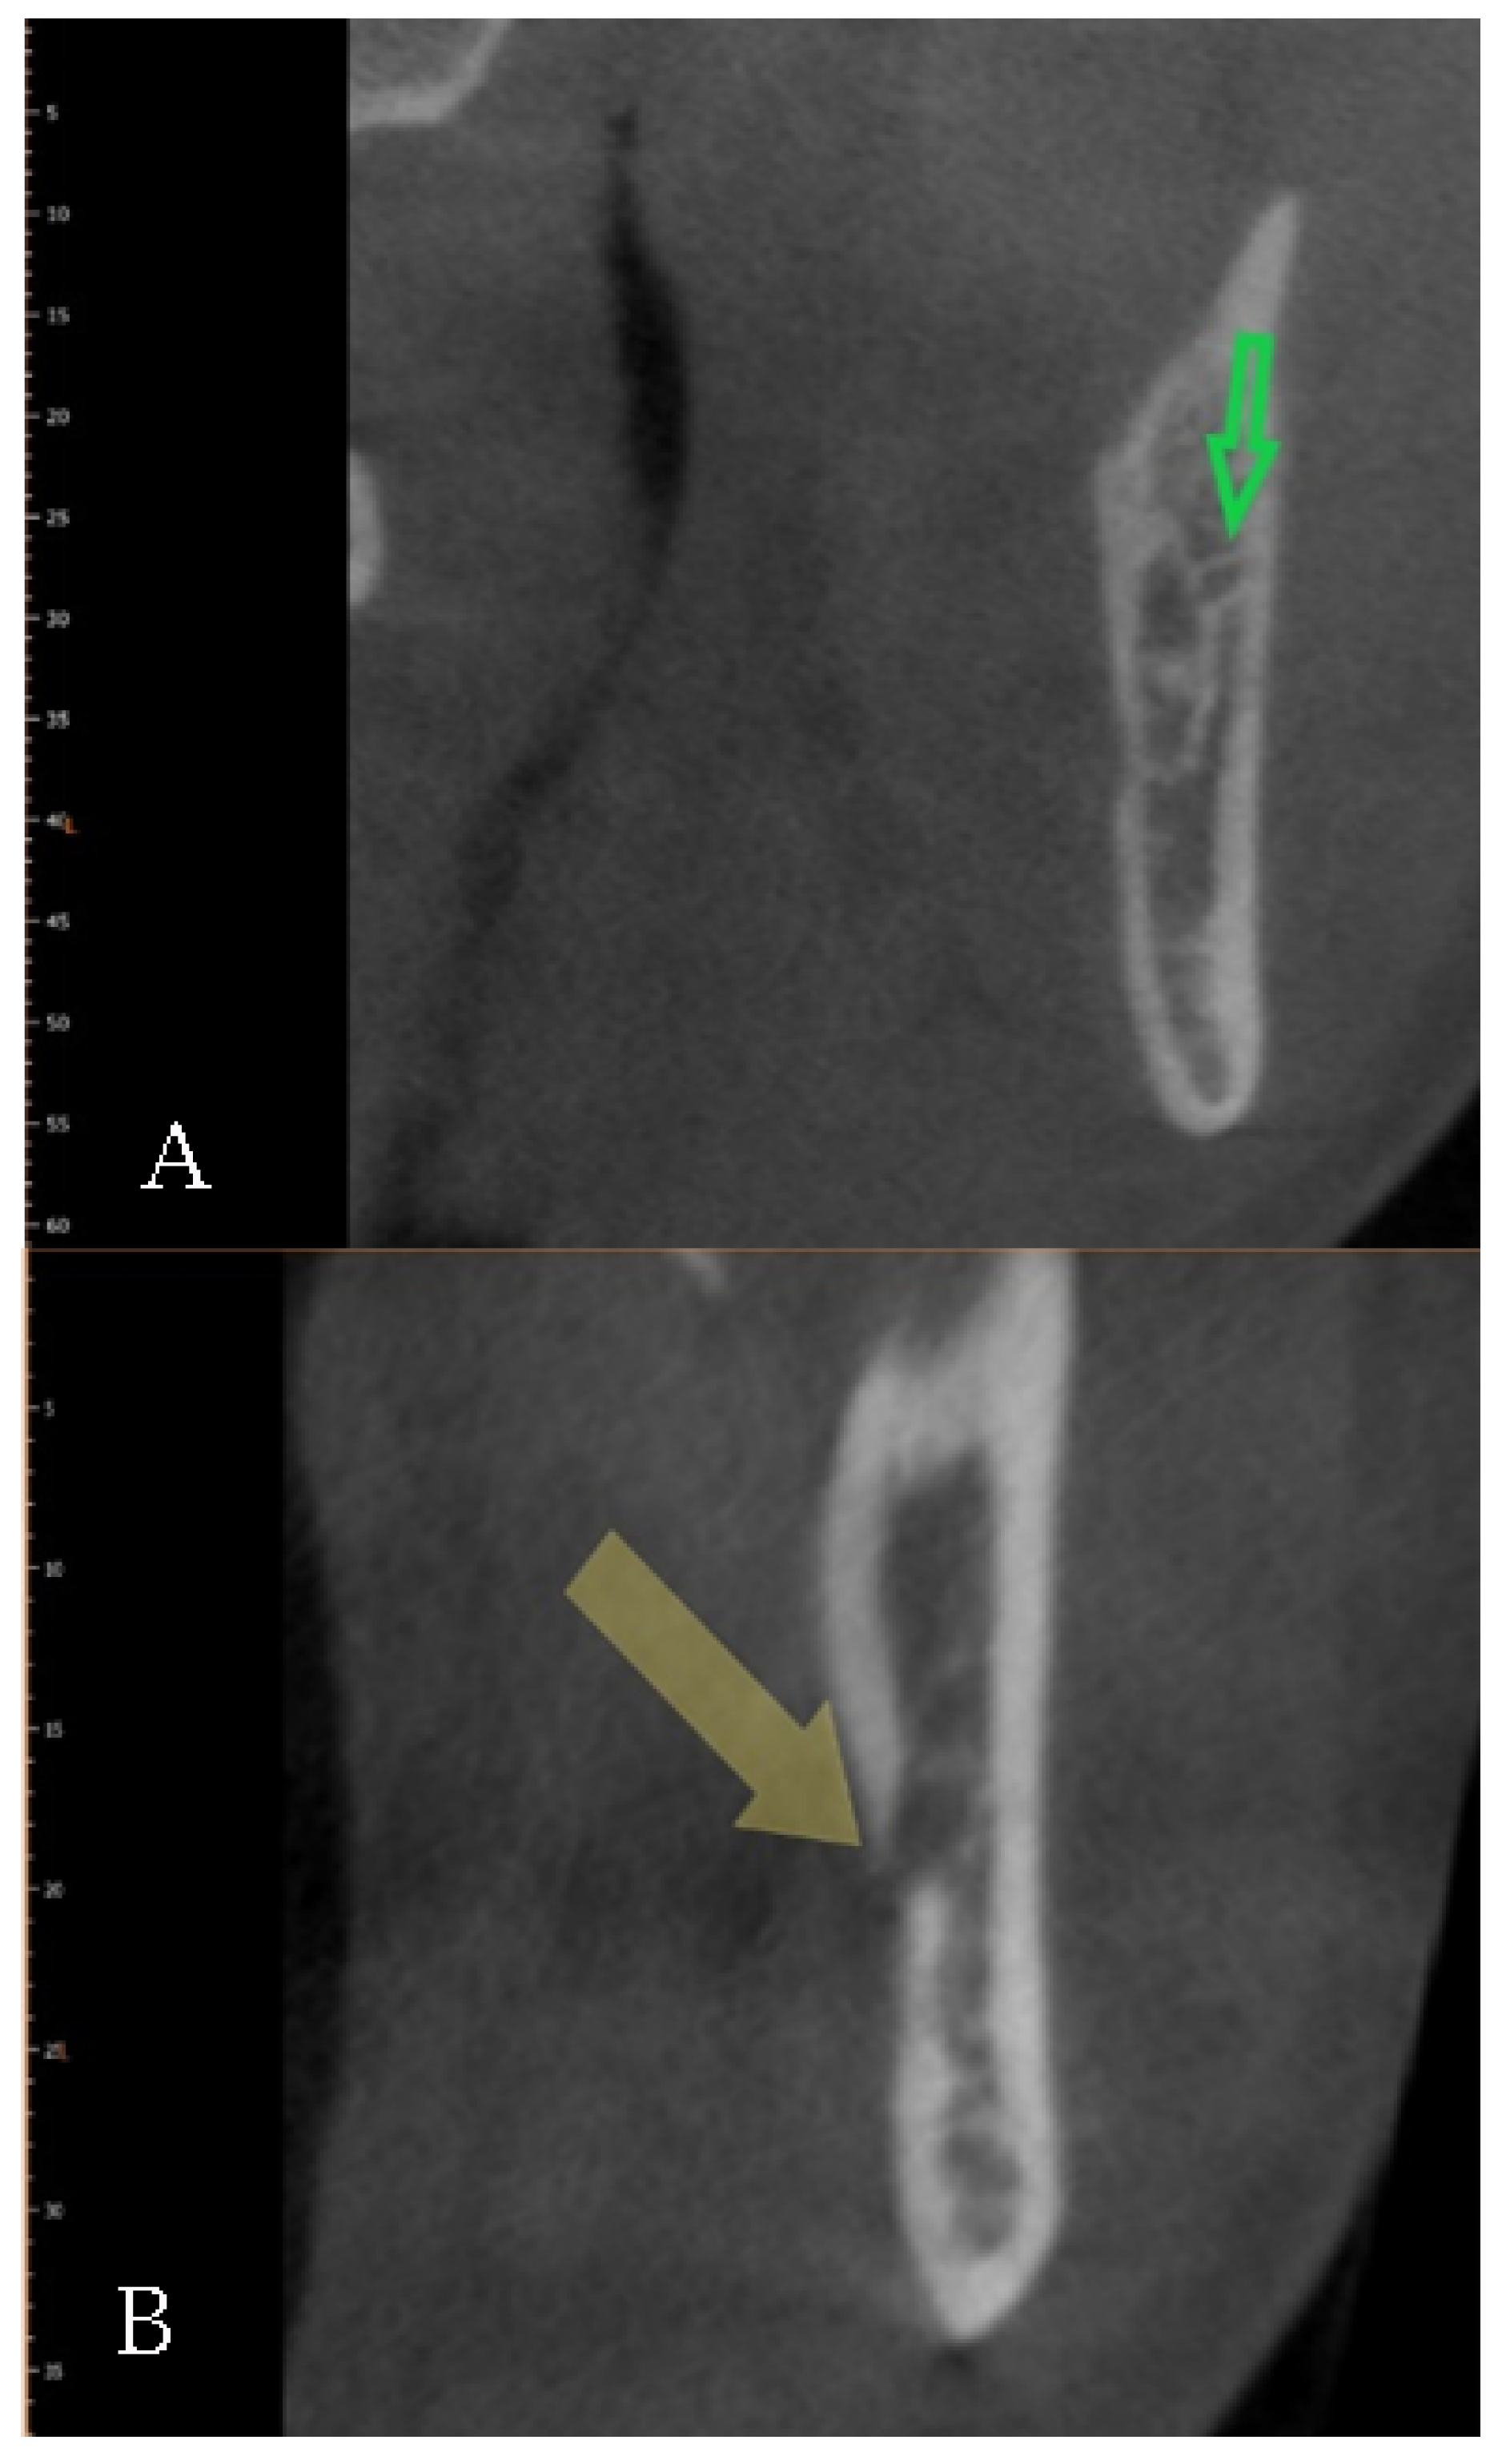

4.2. Bifid Canals: A Difficult Classification, Established Presence, and Clinical Implications of the Morphometric Data